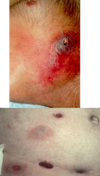

Irritant Contat Dermatitis

- reaction to exposure to toxic substance - can lead to necrosis

- Etiology

- agents, skin type, occupation

- Patho (3 main changes):

- disruption of skin barrier

- epidermal cellular changes

- cytokine relase

- cytotoxic damage to keratinocytes

- Manifestations

- acute presentation (w/in 48hr of exposure): burning, itching, stinging, pain

- physical:

- erythema, vesicles, bulla, burns, necrosis

- sharply demarcated

- unusual configuration

- lesions at various stages

- lasts days to weeks

- Chronic presentation

- dryness, chapping, scaling, fissures (typically on hands)

- Tx:

- remove irritant

- barrier creams

- emolients (Vaseline, lanolin)- form oily layer trapping water on skin

- Ceramide creams- resore epidermal layer

- acute tx:

- wet dressings w/ Burrow’s solution: Al sulfate, acetic acid, Ca carbonate, water- astringent, antiseptic, antipyretic cools and dryes

- topical class I-II gluticosteroid preparations

- severe: oral prednisone

- topical steroids:

- hydrocortisone .5, 1, 2.5%- low potency

- clobetasol .05%- higher potency

- triamcinolone- .025, .1, .5%

- eruption: erythema and edema w/ papules or vesiles/bulla

- evolution: erosions, crusts, scaling

- chronic: papules, scaling, lichenification-excoriations